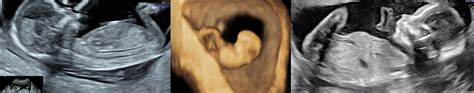

Ramziho metóda, tiež známa ako Ramziho teória, je štúdia, prostredníctvom ktorej sa pozoruje placenta od prvých týždňov tehotenstva. Základom tejto teórie je predpoklad, že umiestnenie placenty v maternici v skorej fáze tehotenstva môže naznačovať pohlavie plodu. Podľa tejto metódy, ak sa placenta formuje na pravej strane maternice, dieťa má s najväčšou pravdepodobnosťou chromozómy XY, čo znamená, že ide o chlapca. Naopak, ak sa placenta tvorí na ľavej strane maternice, predpokladá sa, že pôjde o dievča.

Táto metóda vychádza z pozorovania, ako sú choriové klky (vláknité výrastky, ktoré tvoria časť placenty) lateralizované. Pri farebnom prietokovom doplerovskom ultrazvuku, ktorý by sa mal vykonávať od 6. týždňa tehotenstva, je najjasnejšia oblasť okolo gestačného vaku tá, ktorá sa najviac pozoruje, pretože sa tam placenta vytvorí.